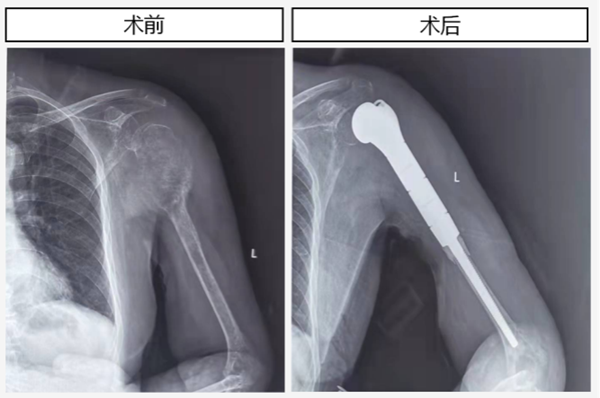

骨一科为左侧肱骨近端巨大转移性肿瘤患者实施保肢手术

近日,骨一科成功完成一例“左侧肱骨近端巨大转移性肿瘤”导致的肱骨近端严重骨破坏伴病理性骨折的人工肱骨头置换术和肩袖重建术,术后患者恢复了肩关节结构及功能。 患者是一名73岁的女性,既往因中度-重度绒毛管状腺瘤行直肠肿瘤根治切除术。...